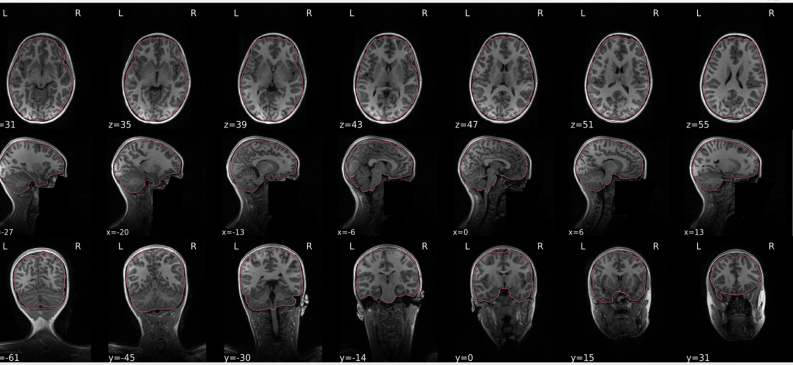

dT1w spatial normalisation

This QC step shows the registration of the T1 image to MNI space.

The registered T1 image is shown in the background with a brain atlas in MNI space as an overlay.

Example of a good subject

- If the registration performed well, you should see an overlap (i.e., correspondence of structures) between the MNI template and the T1 registered to the MNI space.

Example of a bad subject

- In case of poor registration, you should see a misalignment between the MNI template and the T1 (e.g., brain shifted down).

Summary

| good | bad |

|---|---|

| Structures of the MNI template and the registered T1 are well aligned | Structures of the MNI template and the registered T1 aren’t well aligned, e.g. brain is shifted downwards |